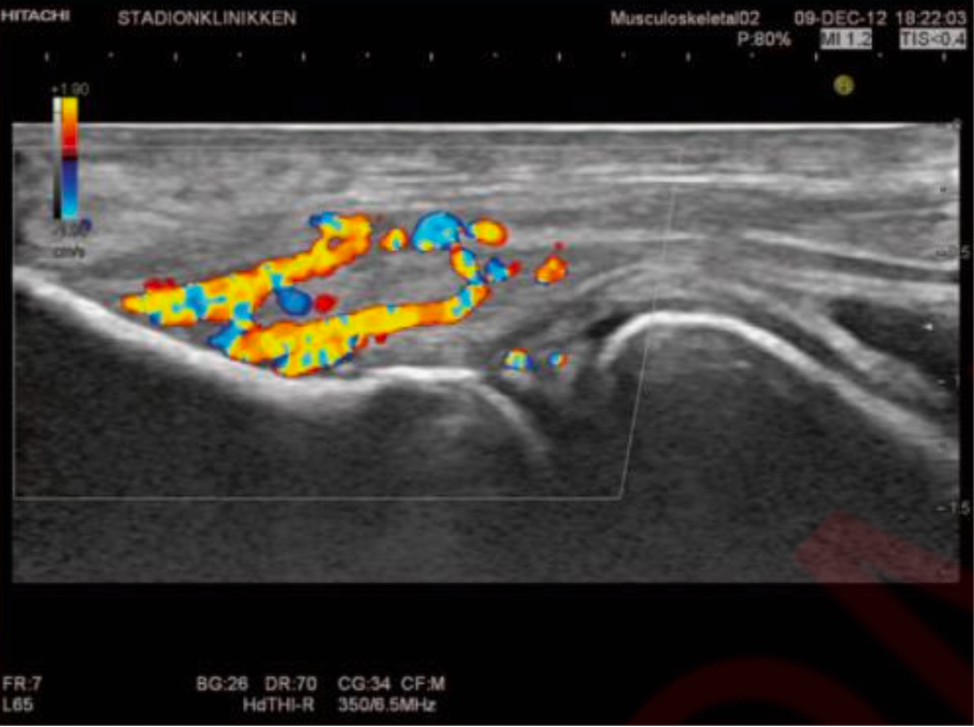

- УЗИ - метод, позволяющий оценить состояние сухожилия (волокнистость, отек, утолщение, кровоснабжение, наличие кальцинатов), место крепления к кости (эрозии), состояние оболочки сустава (выпот, утолщение, кровоснабжение) - все моменты которые нужны для диагностики.

Пример воспаления сухожилий-разгибателей на УЗИ

Применительно к локтевому суставу обычно вовлекается общее сухожилие разгибателей, реже - общее сухожилие сгибателей и сухожилие треглавой мышцы. Примерно в 20% случаев возникает синовит - воспаление оболочки сустава с выпотом, утолщением синовии и усилением кровоснабжения.